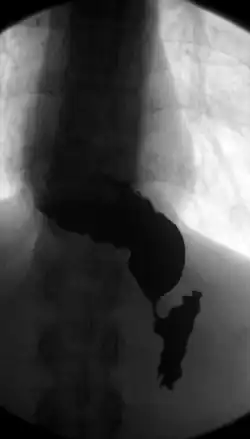

![]() R-контрастный снимок сульфатом бария, видны замедление поступления жидкости в полость желудка через суженный просвет сфинктера и скопление её в расширенном просвете пищевода S-образной формы | |